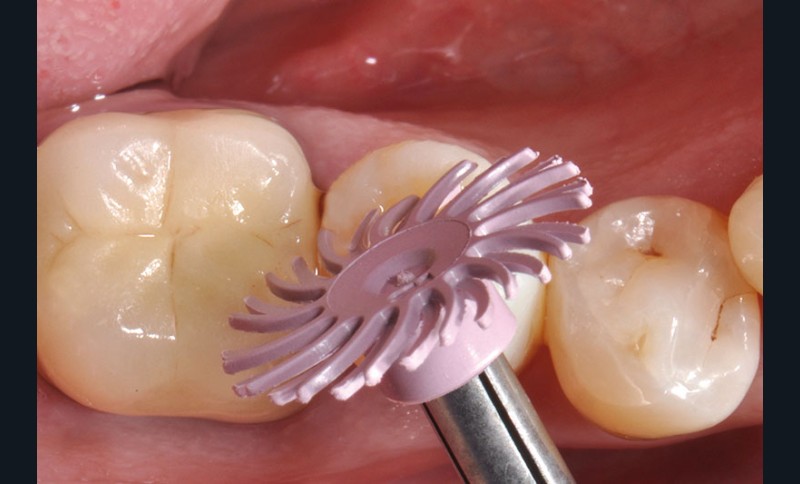

27, 28, 29. La couronne transitoire est pré-polie avec la roue spirale 3M™ Sof-lex™ beige puis polie avec la roue spirale diamantée 3M™ Sof-lex™ rose.